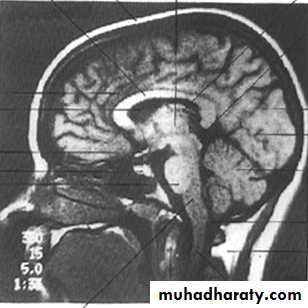

• Coronal (frontal): divides into front and back.• Sagittal: divides into twos sides.

• Planes of Section Neuroanatomy:

Before we can investigate the interior of the brain by cutting it up we need to define the planes of the brain that we will cut (section) in.

Going to a higher horizontal (axial) plane is going rostral. Going down towards the spinal cord and cauda equina is going caudal.

The coronal plane is also known as the frontal plane

Coronal section

Sagittal section